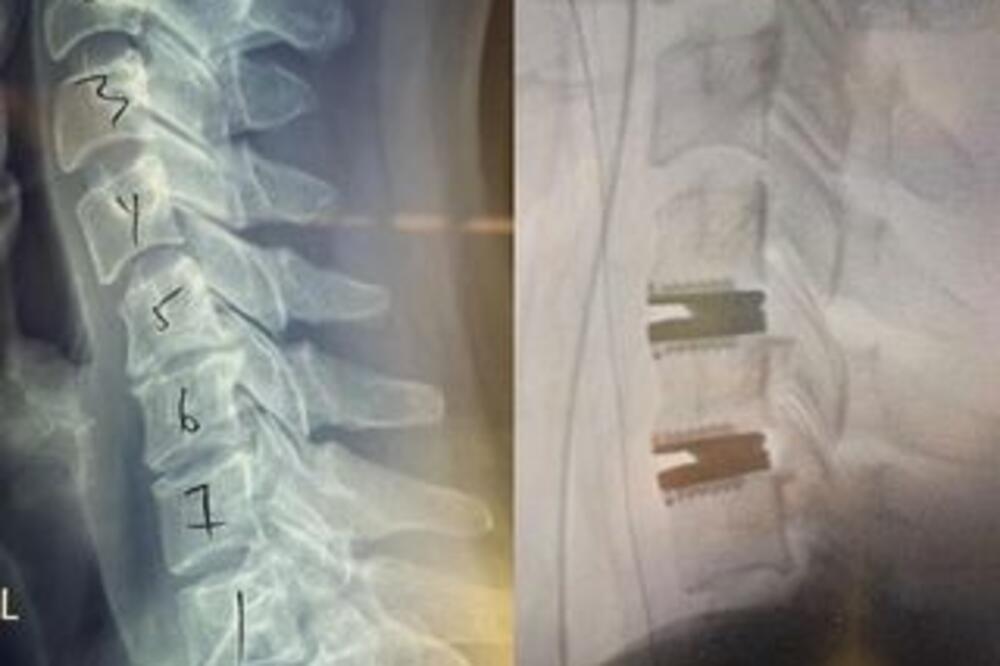

Holivudska glumica Ketrin Higl kaže kako je sada "robot" nakon što je podvrgnuta operaciji vrata kako bi se oslobodila "najnezgodnije boli" koju je ikad osećala.

42-godišnja glumica na Instagramu je podelila fotografije oporavka nakon operacije. "Pa... sada sam robot! Dva titanska diska sad mi stoje u vratu i mogu verovatno stajati na glavi satima... Neću to još pokušavati, ali dajte mi nekoliko meseci i videćete", našalila se.

Iako nije otkrila šta joj se dogodilo, napisala je kako će joj dva titanska diska pružiti "novi život bez bolova".